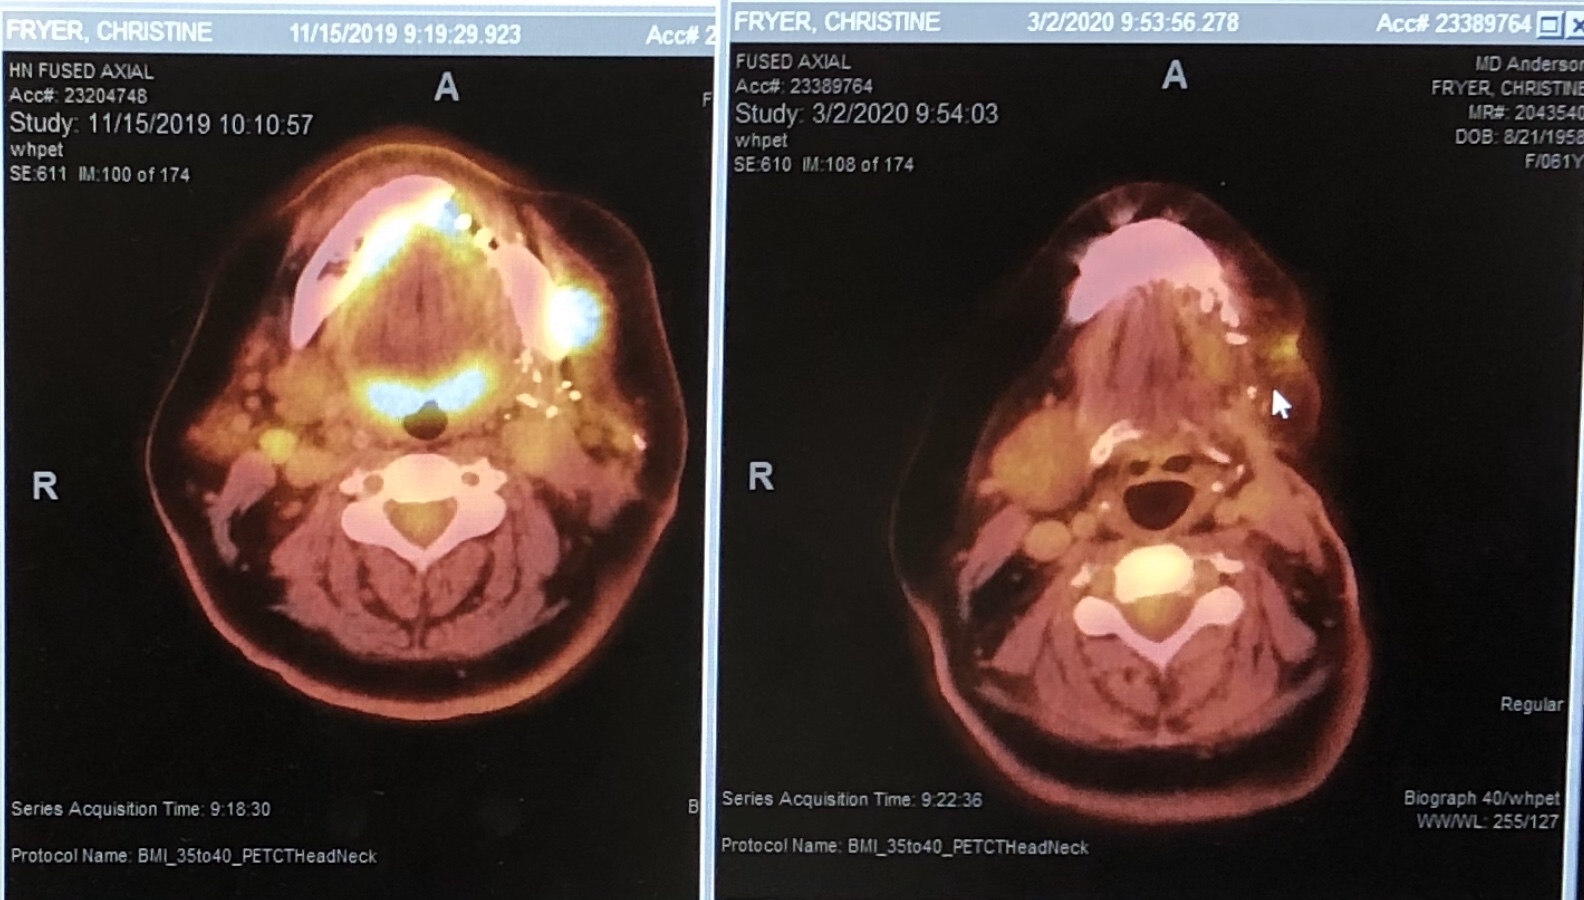

PET Scan

A positron emission tomography scan is an imaging test that helps reveal how your tissues and organs are functioning. A PET scan uses a radioactive drug (tracer) to show this activity.PET ScanA positron emission tomography scan is an imaging test that helps reveal how your tissues and organs are functioning. A PET scan uses a radioactive drug (tracer) to show this activity.

Well, we promised you an update in mid November and we thought it would be the last one. Unfortunately a lot has happened since our trip to UK, visiting parents, kids and grandkids. Sadly, the cancer has returned as a big lump on the left jaw line, close to the original surgery site.

After a series of consultations, CT and PET scans, the plan of attack is to have a series of seven immunotherapy infusions three weeks apart, starting on 17th December, another extensive surgery on 27th December to remove the tumor, and radiation treatment once I have recovered from the surgery.

More CT Scans - February 10th 2020

Since Rob was here for a visit this week, we thought we would treat him to a day at MD Anderson downtown! Although we are not, by any means, out of the woods, we received some encouraging news. Christine had another CT scan today, and scan images (on web page), shows the tumor that was identified on December 19th, has considerably reduced in size after the two rounds of chemotherapy. Dr. Blumenschein was absolutely gobsmacked with these results. Christine will be having a third round of chemotherapy on Wednesday, after which the remaining tumor will be surgically removed on March 13th. We both thank you all very much for your continual support and good wishes. Christine will likely be out of action from Saturday for five or six days due to the fatigue caused by the chemotherapy treatment.